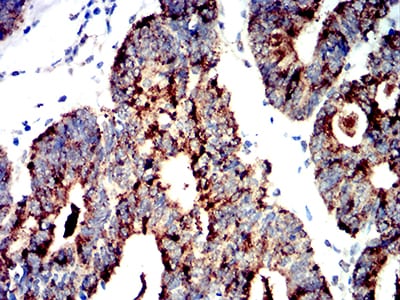

Immunohistochemical analysis of paraffin-embedded human rectum cancer tissues using PRKAA2 mouse mAb with DAB staining.